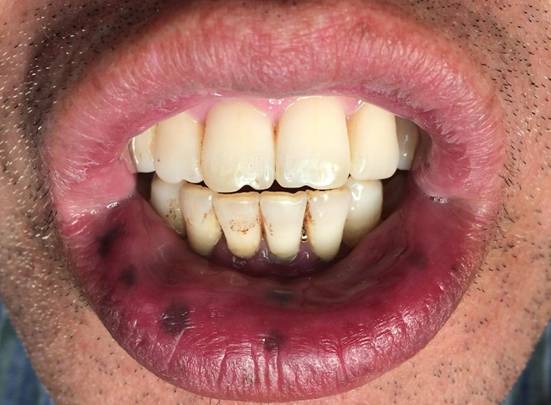

吸烟:吸烟导致口腔黏膜发黑的原理跟食物类似,口腔黏膜发黑的同时在牙齿上也能发现很多烟斑。与食物稍有差异的是,吸烟导致的黏膜发黑大部分发生在口腔下半区,包括下牙区、下嘴唇,这可能跟吸烟的方式有关(图2)。

图2:吸烟导致下嘴唇和下牙龈发黑,同时下牙也见到色素沉着。